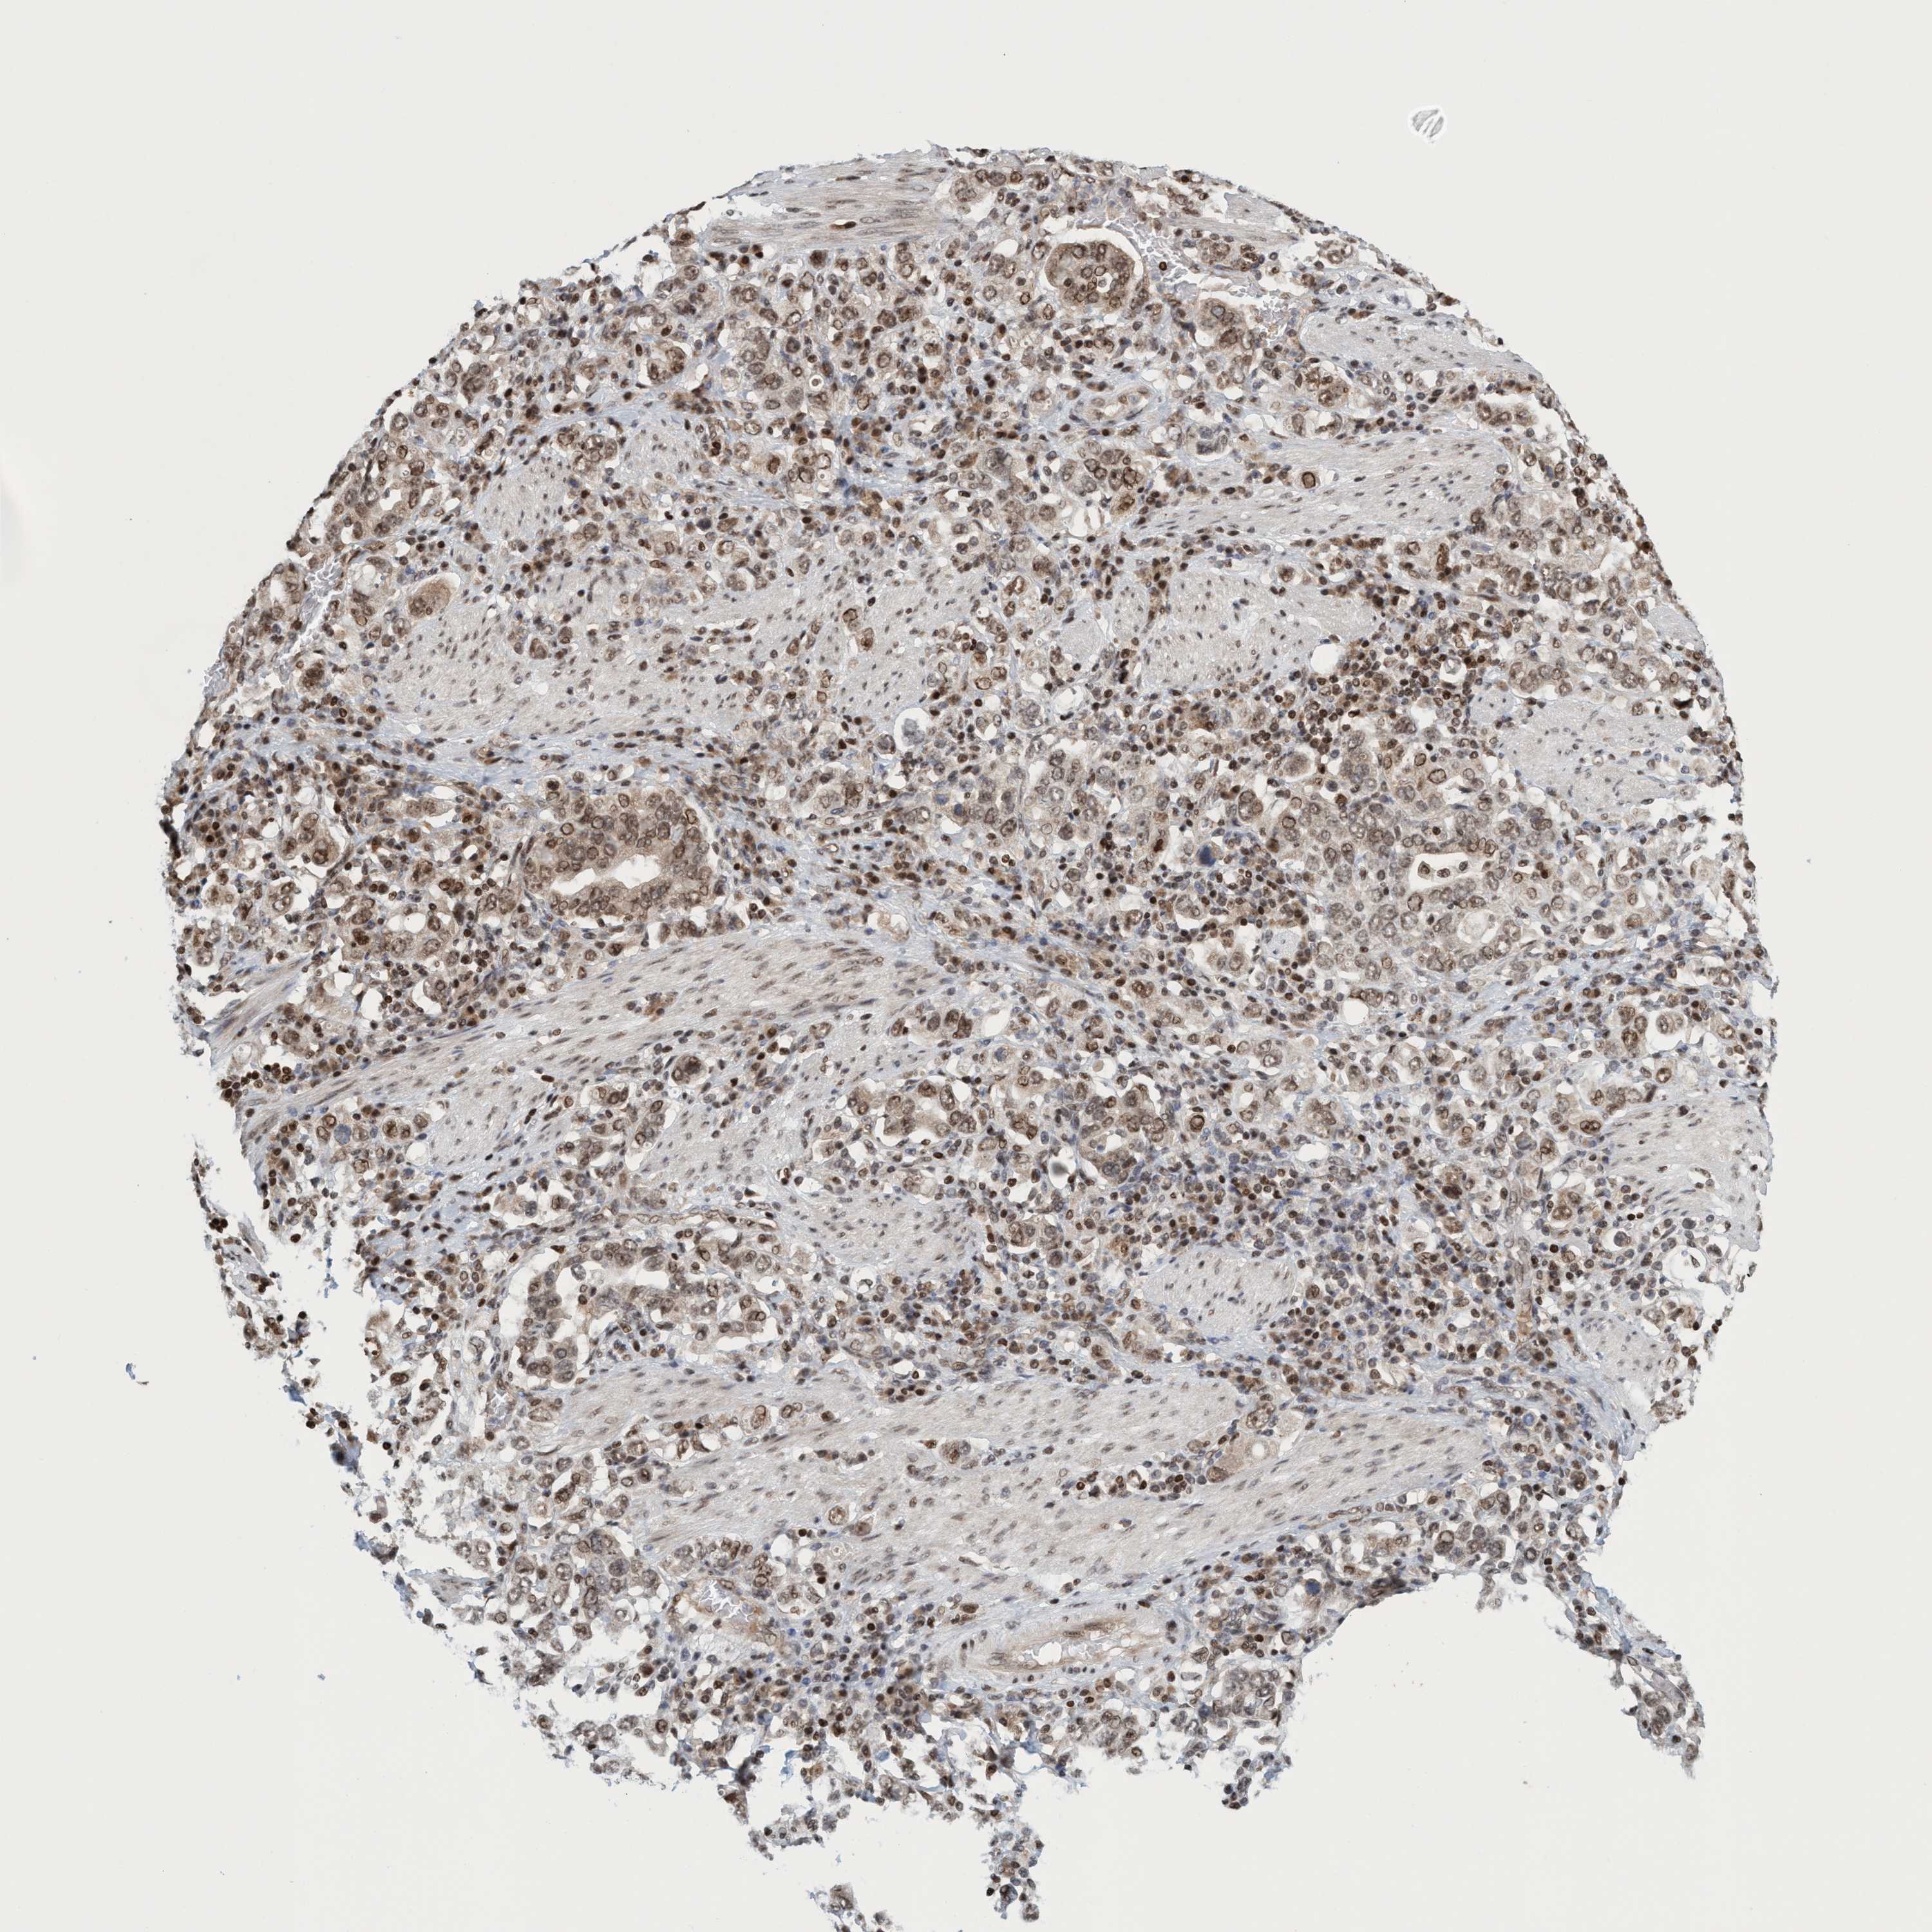

STOMACH CANCER - Protein expressioni

A mouse-over function shows sample information and annotation data. Click on an image to view it in a full screen mode. Samples can be filtered based on level of antibody staining by selecting one or several of the following categories: high, medium, low and not detected. The assay and annotation is described here.

Note that samples used for immunohistochemistry by the Human Protein Atlas do not correspond to samples in the TCGA dataset.

Antibody stainingi

Antibody staining in the annotated cell types in the current human tissue is reported as not detected, low, medium, or high, based on conventional immunohistochemistry profiling in selected tissues. This score is based on the combination of the staining intensity and fraction of stained cells.

Each image is clickable and will lead to virtual microscopy that enables deeper exploration of all samples and also displays staining intensity scores, fraction scores and subcellular localization as well as patient and tissue information for each sample.

Antibody HPA021557

Antibody HPA024646

Staining

High

Medium

Low

Not detected

Intensity

Strong

Moderate

Weak

Negative

Quantity

>75%

75%-25%

<25%

None

Location

Nuclear

Cytoplasmic/membranous

Cytoplasmic/membranous,nuclear

Adenocarcinoma, NOS